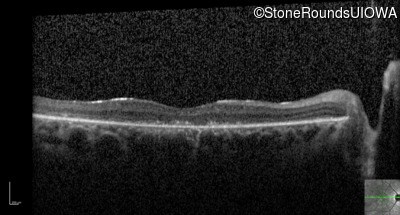

Optical Coherence Tomography - Right - 10/140 sc

Exemplar / OCT Stack